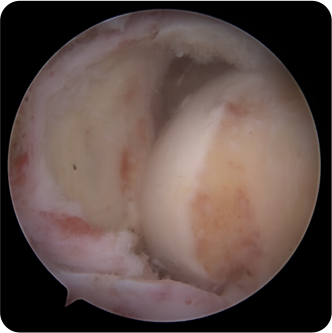

회전근개파열의 여러 모습들

어깨의 회전근개파열은 통증이 심했다가도 좋아지거나, 처음부터 통증이 없을 수도 있기 때문에 많은사람들이 방치를 하는 경우가 많습니다.

회전근개가 완전히 파열되었고 오랜시간이 경과한 경우에는 끊어진 힘줄이 말려 들어가서 봉합이 불가능하거나

어깨 전체의 근육 위축을 유발할수있습니다.